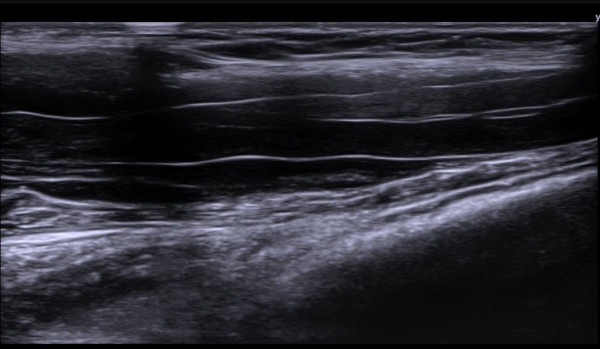

Á¤Á߽Űæ Ⱦ´Ü¸é°Ë»ç¿¡¼­µµ Á¤Á߽ŰæÀÌ Àú¿¡ÄÚ ºÎÁ¾ÀÌ ±æ°Ô  °üÂûµÇ°í ½ÇÁú³» ƯÁ¤ ¼¶À¯¼ÒÀÇ

Àú¿¡ÄÚ ºÎÁ¾ÀÌ ¶Ñ·ÇÇÏ´Ù(»çÁø 5, 6).